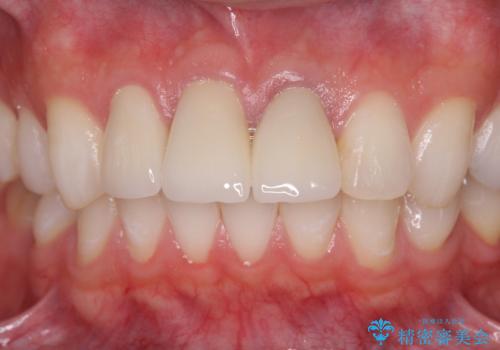

前歯の変色 審美性の改善

歯の挺出を行ったことで歯ぐきの腫れも改善され、安定した歯周環境下でのセラミッククラウン治療を行うことができました。